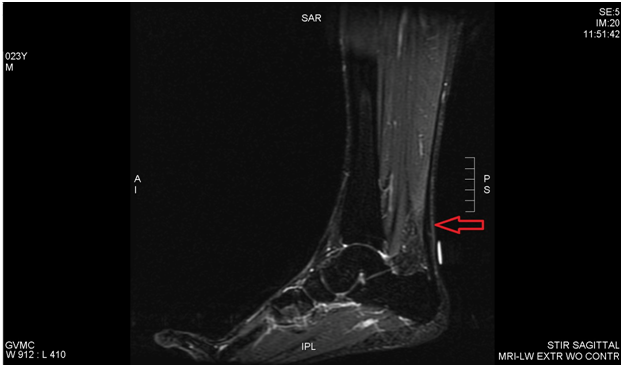

We report a case of Achilles tendinosis that was treated with a high volume, hydrodissection visualized by conventional B-mode ultrasound. Prior MRI revealed a thickened right Achilles tendon with a small defect. Ultrasound examination showed a thickened Achilles tendon with physical exam revealing a prominent Haglund’s deformity, mild fusiform swelling and pain along the posterior Achilles (Figure 1 & 2). The condition had been poorly responsive to standard management including protected ambulation in a cam walker boot, anti-inflammatory medication, modalities and therapeutic exercise, as well as a platelet rich plasma injection. We suggest using high volume ultrasound guided injection adjacent to (anterior to) the Achilles tendon as an adjunct to treat this difficult clinical syndrome.

Figure 1 T2, sagittal imaging shows prominent Haglund’s deformity and fusiform swelling.